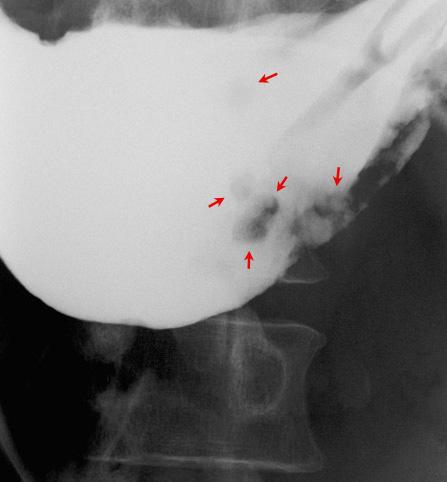

“사마귀”모양의 융기가 다발한 위의 과형성 용종

종양양 병변/과형성 용종

위(부위)/2개 이상

X-P

10~14